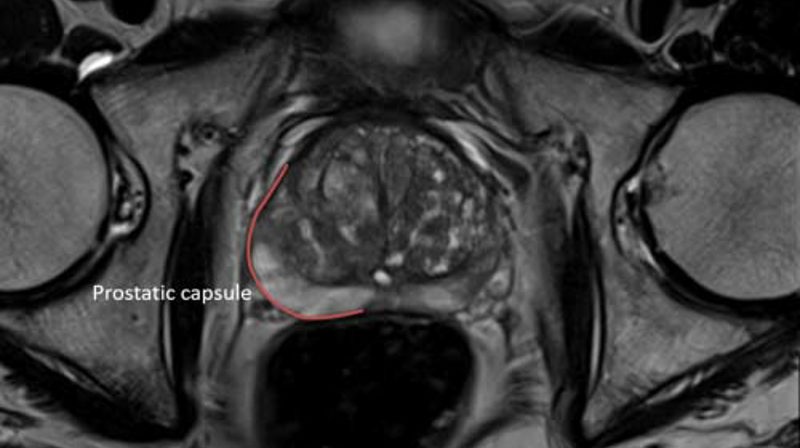

mpMRI before biopsy

We believe mpMRI before biopsy offer the potential for a step-change in prostate cancer diagnosis, and we're working to support it's roll out.